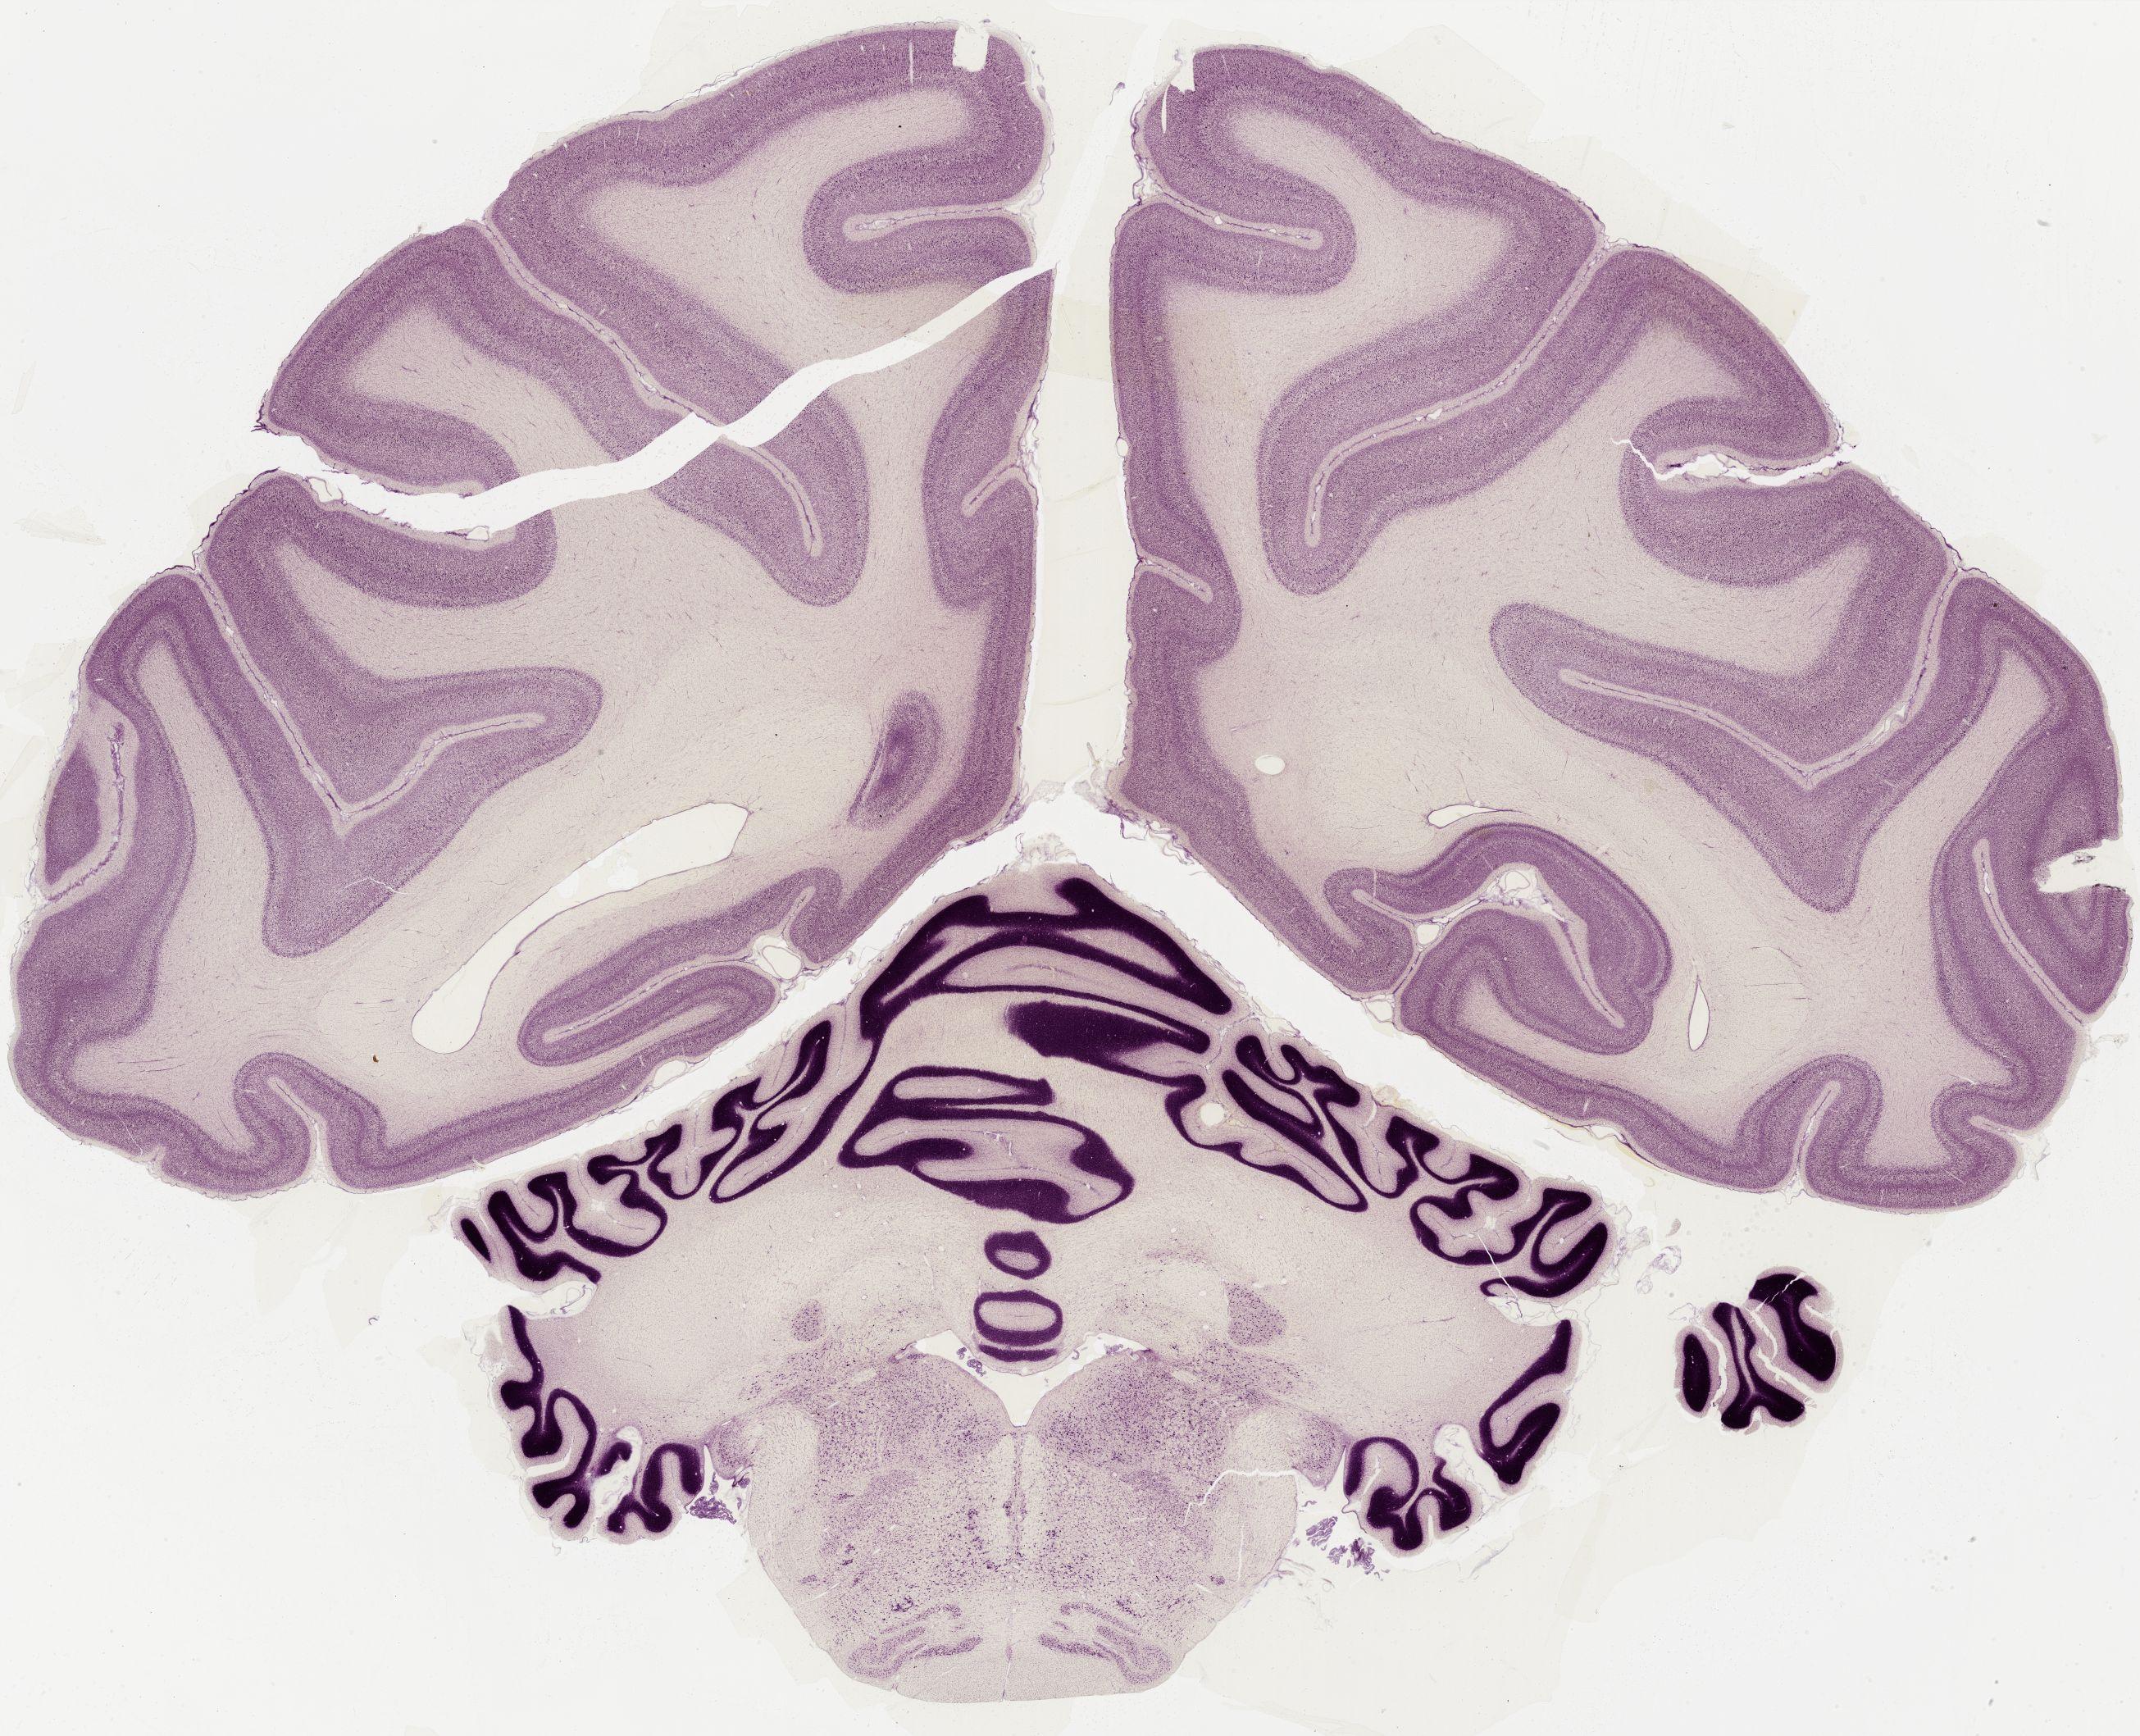

Datasets -> Macaca Mulatta -> Nissl, coronal, histo, Whole-Brain, adult

[ Metadata ]   ·   Source: Edward G. Jones

thumbnail

0601 - labeled